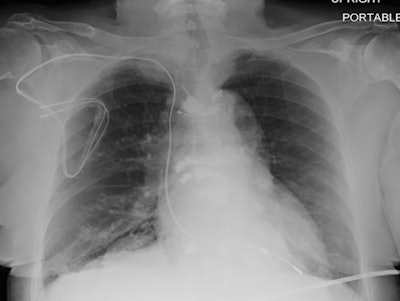

The PROMeNADE study enrolled 532 patients with non-MRI conditional devices, including products manufactured by Medtronic, Abbott, and Boston Scientific. In total, the enrollees had 608 MRI clinically necessary studies, of which 61 were cardiac MRIs. Researchers excluded patients with ICDs implanted before 2000 or pacemakers implanted before 1998.

Precautions were taken during the imaging studies, including monitoring of patients for abnormalities and asynchronous pacing for the 27% of patients who were pacemaker-dependent. Studies were most commonly ordered for evaluation of the head and spine, followed by the hips/pelvis and shoulder or knee.

Safety is particularly of concern for MRI studies of organs that are closer to an implanted device. But, importantly, no adverse events were reported for 83 MRI studies of the thoracoabdominal region.